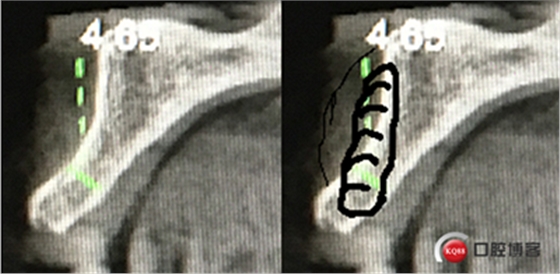

“以修復(fù)為導(dǎo)向”,在前牙種植體中心點(diǎn)就是未來(lái)牙冠舌側(cè)窩位置。那這個(gè)病例植體的方向和位置就只能是下圖右側(cè)這樣了。很明顯植體根尖部分要穿出唇側(cè)倒凹的。怎么辦?翻大瓣植骨蓋膜減張縫合?不!可以不翻瓣,大家仔細(xì)看看下圖右圖我畫(huà)的那條細(xì)細(xì)的弧線,是不是跟原來(lái)唇側(cè)凹陷的骨面成為左右對(duì)稱(chēng)的兩條弧,也就是說(shuō)骨膜從原來(lái)唇側(cè)凹陷骨面上剝離然后放到左側(cè)我畫(huà)的那條弧線那里根本不需要減張,這兩條弧線之間也就是唇側(cè)凹陷處放上骨粉,骨膜不會(huì)增加張力。不知道大家看明白了沒(méi)有。